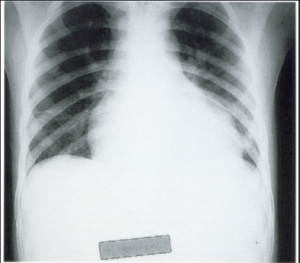

A 3-year-old child is admitted to the hospital due to decreased appetite and weight loss. She has been afebrile, and has not had vomiting or diarrhea.

Her activity level has decreased over the past two weeks.

She had been healthy until 2 months ago, when she was hospitalized for 48 ...

infection with mild respiratory distress and poor fluid intake.